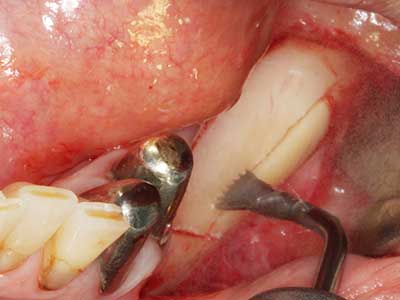

Bei der Knochenblockentnahme zeigen sich weitere Vorteile für die Piezochirurgie: Neben der bereits beschriebenen hohen Präzision bei der Osteotomie stellt sich gerade die Verwendung der dünnen Sägespitzen als besonders materialschonend heraus. Bei der Verwendung insbesondere von Lindemannfräsen sind mit deutlich höheren Entnahmeverlusten durch die dickere Instrumentenspitze zu rechnen (Lakshmiganthan, Gokulanathan et al. 2012). Die insbesondere bei retromolar entnommenen Blocktransplantaten notwendige basale Abtrennung wird durch speziell hierfür vorgesehene rechtwinklige Sägen erleichtert, so dass die Piezochirurgie als präzises, übersichtliches und sicheres Verfahren zur retromolaren Knochenblockgewinnung angesehen wird (Happe 2007) (Abb. 1-12).